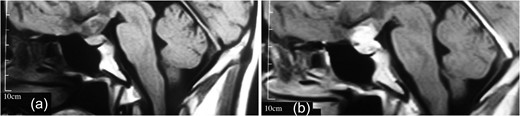

MRI showing (a) an intrasellar lesion isointense in T1W and T2W images enhancing homogenously and mildly after contrast material injection and (b) a suprasellar lesion 3 × 3 × 2 cm in diameter with the same intensity in T1W and T2W images which enhanced notably after contrast material injection.